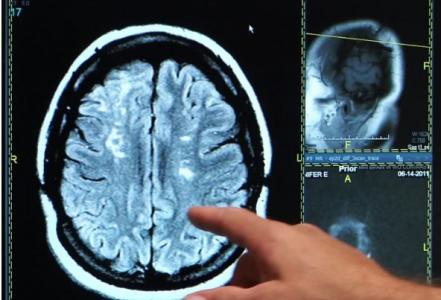

AVC : La molécule qui redonne de la plasticité cérébrale

Cette découverte d’une équipe de l’Université de Göteborg pourrait permettre une récupération plus rapide et plus efficace après un accident vasculaire cérébral (AVC). Il s’agit d’une « simple » molécule, « C3a peptide », produite naturellement dans le corps. C3a a la capacité de créer de nouvelles synapses dans le cerveau. Ces données obtenues à ce stade chez l’animal et présentées dans la revue Brain confirment l’efficacité du composé.

Les chercheurs suédois administrent C3a ou un placebo à 28 souris, modèles d'AVC, une semaine après l'événement, et via des gouttes nasales. Les souris traitées récupèrent beaucoup mieux et plus rapidement : concrètement, elles sont capables d'utiliser à nouveau la patte paralysée par l'AVC. L'analyse montre également que C3a permet, en fait, la génération de nouvelles cellules nerveuses et la création de nouvelles synapses entre les cellules. Un processus que beaucoup considèrent comme clé pour la récupération de la fonction cérébrale.